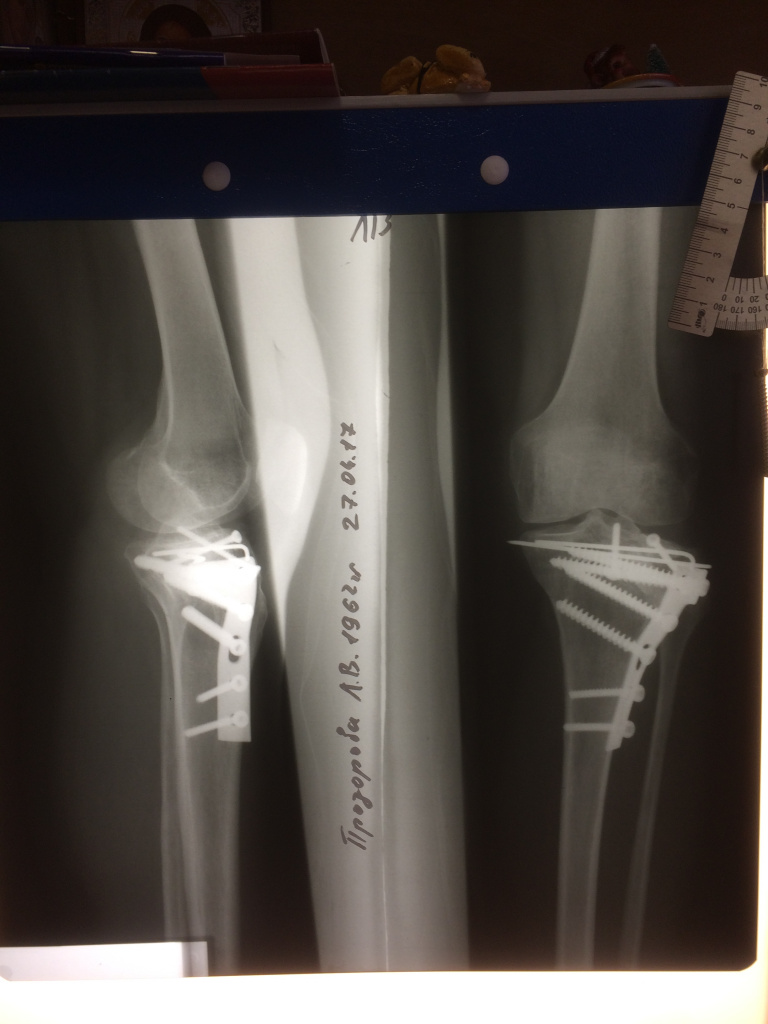

Использование материала Остеоматрикс при импрессионном оскольчатом переломе наружного мыщелка большеберцовой кости по типу Schatzker II

Использование материала Остеоматрикс при импрессионном оскольчатом переломе наружного мыщелка большеберцовой кости по типу Schatzker II.

Операция - открытая репозиция, остеосинтез большеберцовой кости опорной пластиной с костной ксенопластикой маетриалом "Остеоматрикс". На контрольных снимках в три и шесть месяцев имеется консолидация перелома, миграции фиксатора нет, имеется остеоинтеграция ксенопластического материала. Функция коленного сустава полная.